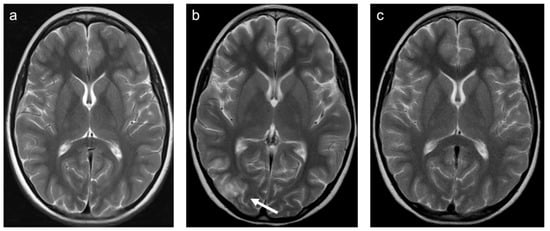

Group 1 consisted of 40 patients. Twenty-five (63%) patients suffered from multiple sclerosis (MS) and nine (23%) from acute demyelinating encephalomyelitis (ADEM). Three patients were diagnosed with a clinically isolated syndrome, one with limbic encephalitis, one with Rasmussen’s encephalitis, and one with vasculitis. Representative cases are shown in Figure 3. A total of 63% of patients were female and the mean age was 14.0 years (min 2.6 years; max 18.4 years). All but one patient were examined with contrast-enhanced MRI and 44% of those examinations showed at least one enhancing lesion. WMSAs were localized supratentorial in 65% of patients and supra- and infratentorial in 35% of patients. There were no isolated infratentorial lesions. In total, 90% of patients had multifocal WMSAs.

Figure 3. Representative case “Autoimmune disorders”: MS. FLAIR (a), T1W pre- and post-contrast (b,c) sequences. Fifteen-year-old girl diagnosed with MS. MRI shows characteristic ovoid/round lesions with asymmetric distribution abutting the lateral ventricles (periventricular) and touching the cortex (juxtacortical) [19] (a). Contrast-enhancing lesions in T1W post-contrast sequences are considered markers of blood–brain barrier breakdown (c).